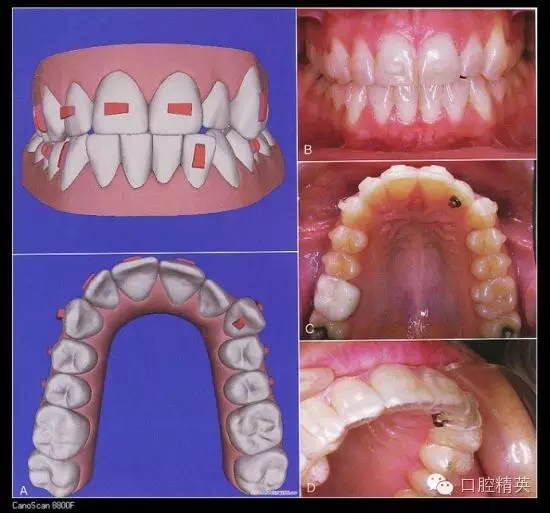

五、隱形矯治器

Invisalign隱形矯治器的原理是先在計(jì)算機(jī)里對(duì)醫(yī)生的印模進(jìn)行三維建模,按照正畸醫(yī)生的指導(dǎo)來設(shè)計(jì)挪動(dòng)牙齒,得到醫(yī)生的確認(rèn)后投入加工。每付矯治器少量移動(dòng)牙齒,兩周更換一副矯治器,在1-2年后完成牙齒的矯治。因?yàn)椴馁|(zhì)沒有金屬,受到很多白領(lǐng)的追捧,不過目前還不能夠治療所有的復(fù)雜病例。對(duì)付輕中度擁擠,輕度開合,牙縫散開等是不錯(cuò)的選擇。